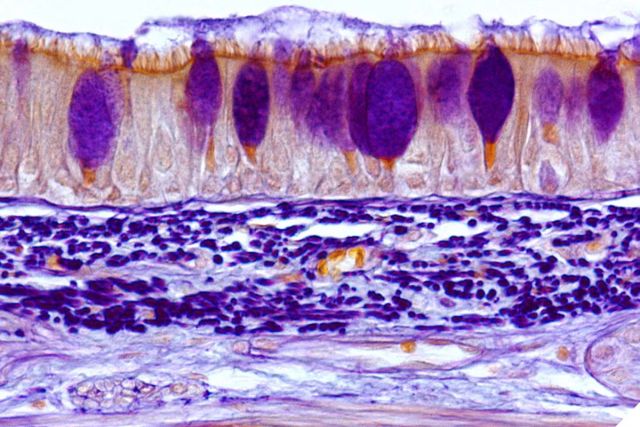

The respiratory airway is lined with beating ciliated cells (the orange hairlike projections) over which a layer of mucus flows. The combination serves to trap and move foreign bodies, including bacteria, in the airway

This lack of clarity stems largely from the fact that the mammalian respiratory system is highly evolved to clear the airways by trapping and sweeping away foreign objects, thanks to a layer of mucus that traps foreign bodies — from dust particles to pathogens — atop a constantly beating layer of hairlike projections called cilia. The question was, how do these bacteria manage to bypass that defense?